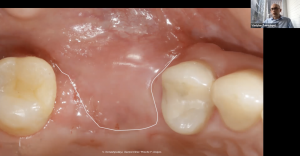

Операционный микроскоп является штатным оборудованием любого стоматологического кабинета. Работа с микроскопом позволяет хирургу стоматологу избавить своих пациентов от необоснованных страданий, а так же работать эргономично, что сохраняет здоровье доктора на долгие годы. Информация, полученная на данном вебинаре, позволит Вам лучше разобраться с необходимыми характеристиками микроскопа и знать основные понятия при работе с таким оптическим устройством. Материал вебинара предоставляет фактические рекомендации по работе хирурга-стоматолога с различным уровнем навыка, от старта до микрохимрургических манипуляций. Дан обзор некоторых возможных, при работе с операционным микроскопом, мало-инвызивных методов аугментации кости и манипуляций мягкими тканями.